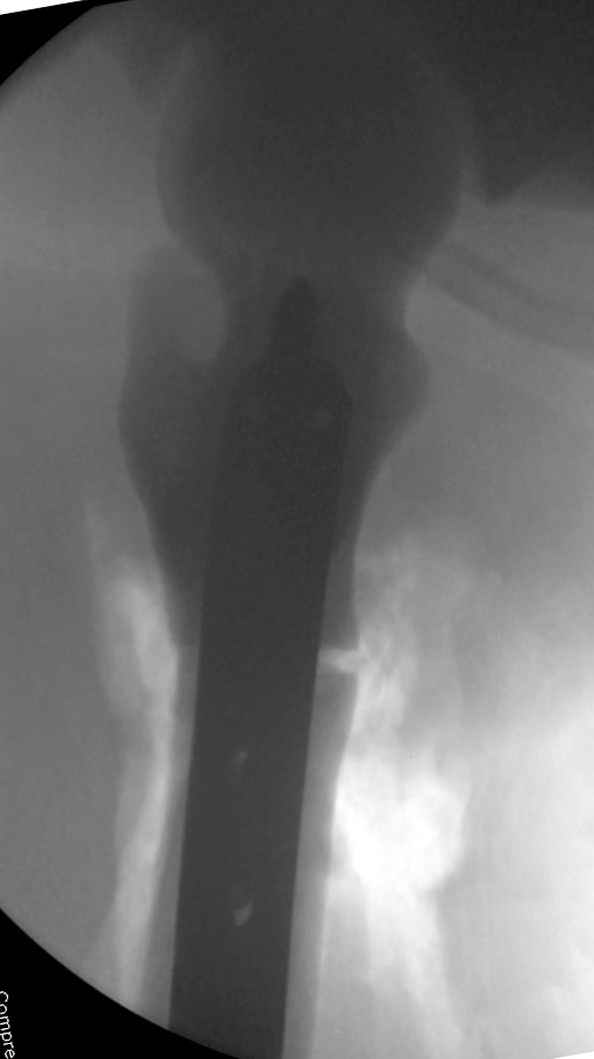

После неудачной попытки скелетного вытяжения в первом мед.учреждении, после осмотра снимков и изучения истории, поставили диагноз “Остеопетроз” или мраморная болезнь, редкая наследственная костная паталогия, где имеется нарушение формации остеокластов.

Конечно, было бы идеальным применение интрамедуллярного остеосинтеза, но учитывая прежний собственный опыт (лечил перелом бедра) и

публикации, предупреждающие о трудностях при обработке кости (иногда из-за неподготовленности инструментария результатом была неадекватная фиксация перелома, или перенос операции из-за фактора усталости оперирующего персонала), решили применить пластину (и в этом же случае был выбран Synthes plate, так что представитель за два дня

зароботал... на десерт тоже).

Заказаны были дополнительные различные дрели, и на следующий день, усиленной бригадой, больного прооперировали, потратив на каждое отверстие около 25-35 минут, хотя сверлили с охлаждением по нарастающей по диаметру сверл и с их заменой каждые 2 мм сверления.

Теперь стоит задача со сращением перелома, из-за отсутствия литературных данных по применению костных стимуляторов при остеопетрозе, и не зная как поведет в этой среде Grafton, все таки надеюсь, что даст толчок к стимуляцию, решил применить пастообразную деминерализованную костную матрицу, расположив спереди между отломками.